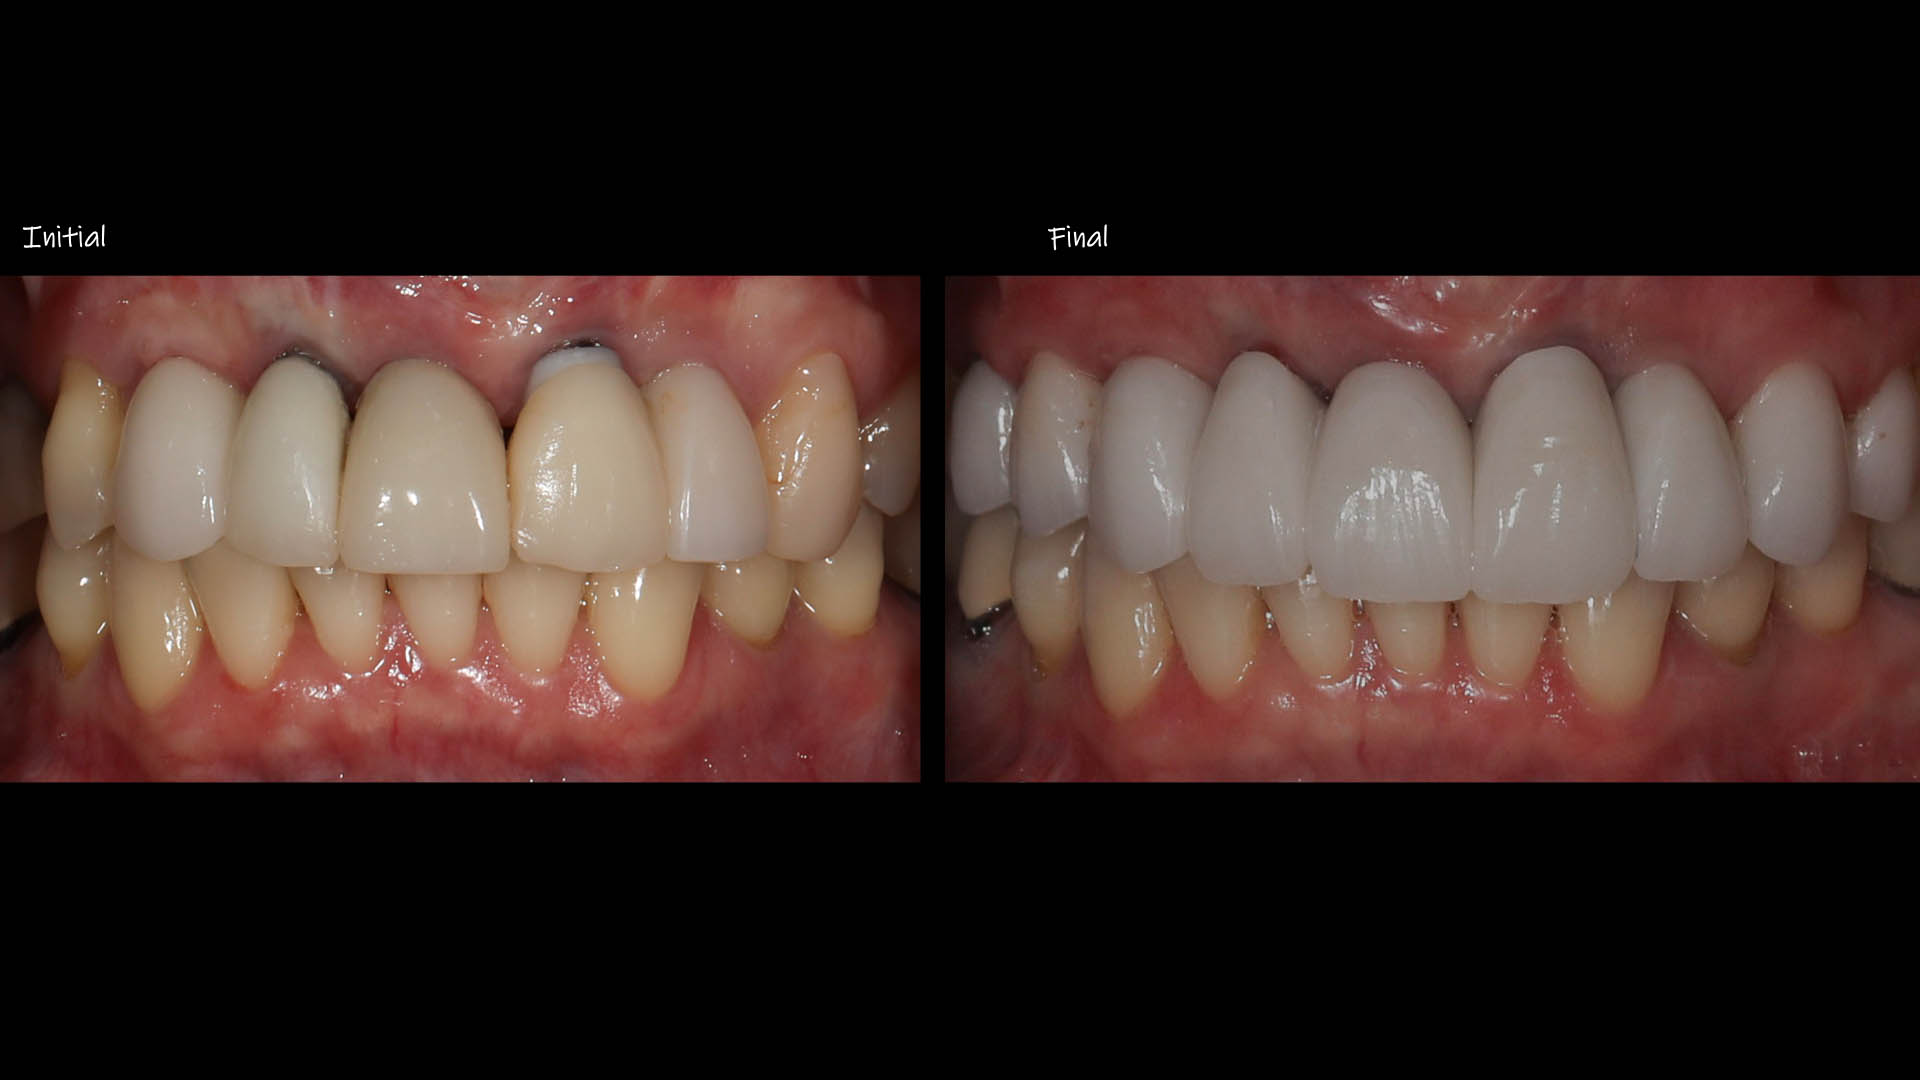

Take a glimpse into the magic of Coral Gables Dentistry through our before and after pictures. See firsthand the incredible smile makeover transformations that have brought confidence and joy to our patients.